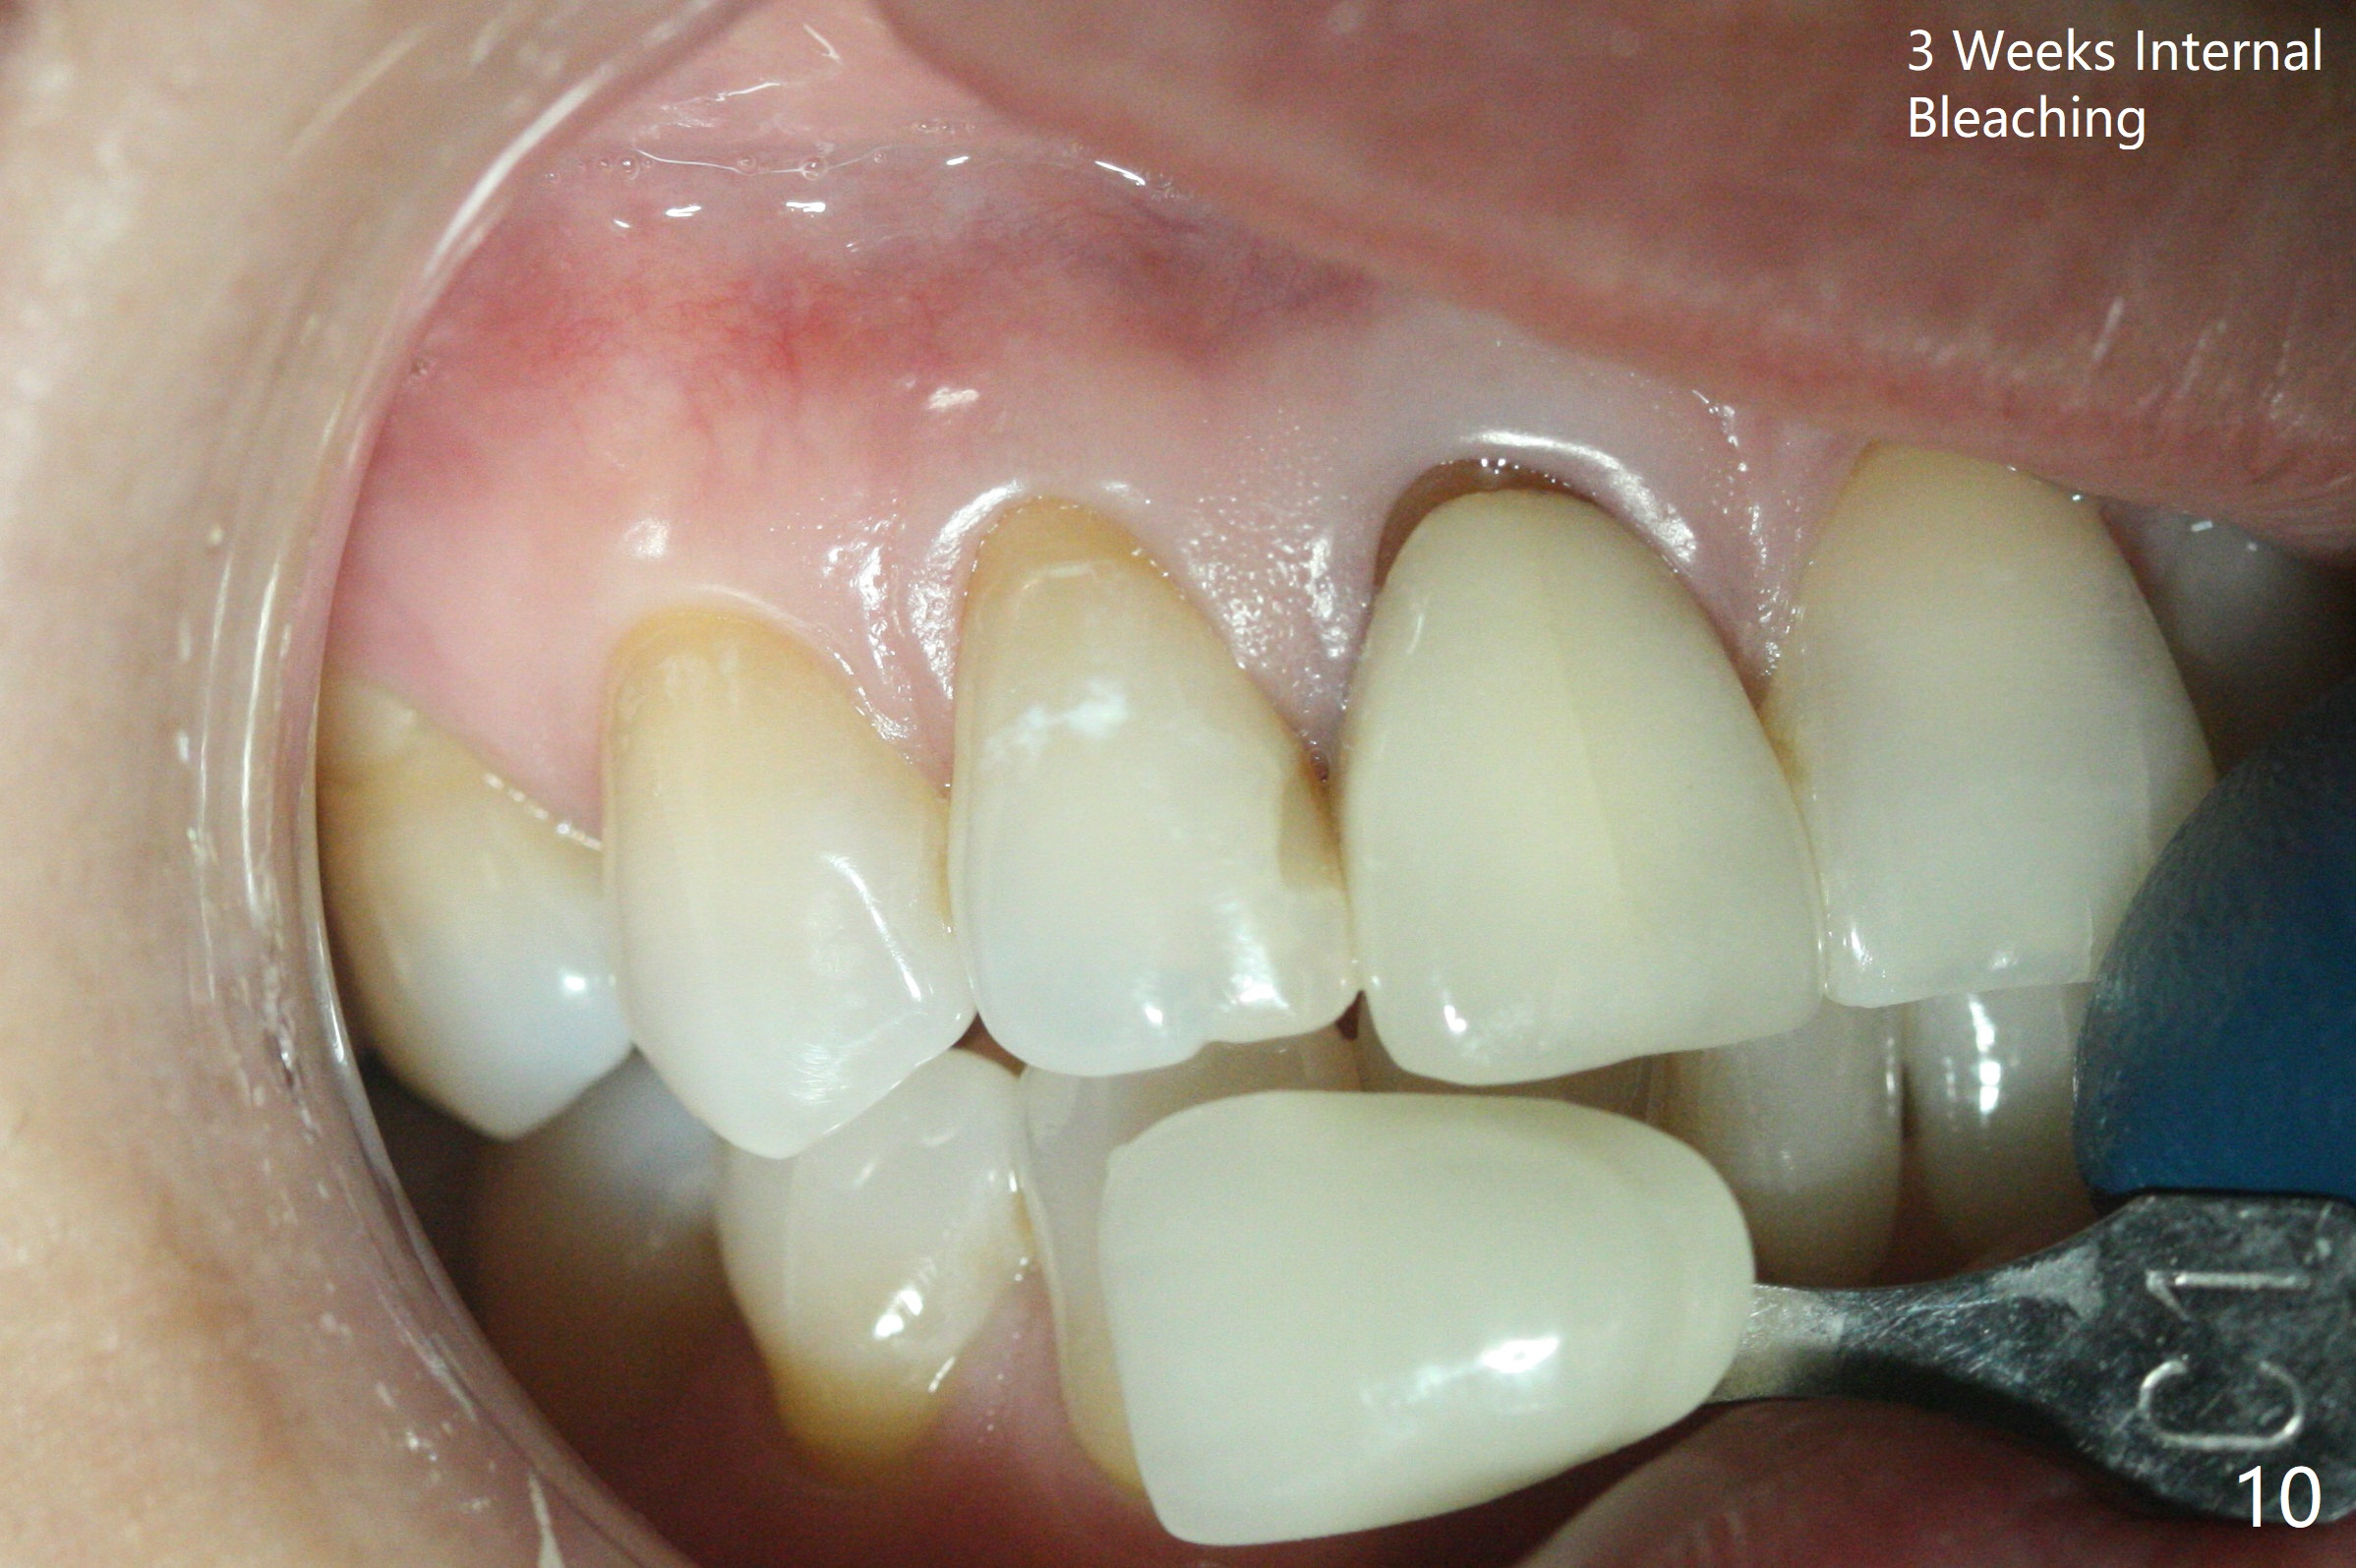

A 46-year-old woman requests a crown for the discolored tooth #7 (Fig.1,2) with mesiolingual composite (Fig.3 C) and periapical radiolucency (*). After RCT (Fig.4,5) with sodium hypochlorite, the tooth #7 is whiter than the ML composite (Fig.6,7). The patient returns 1 day post RCT for in house internal and external bleaching (Fig.8) with 35% hydrogen peroxide gel closed in the canal when she leaves. Three weeks later, the lateral incisor has the shade as the neighboring natural teeth (Fig.9,10). After the lightest shade composite placed in the canal and the access hole (Fig.11), the lateral looks better than the central with a crown and cervical discoloration (Fig.12).